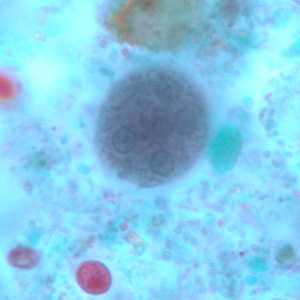

E. coli cysts stained with trichrome.

Figure A: Immature cyst of E. coli, stained with trichrome. Notice the presence of only two nuclei, and a large glycogen vacuole.